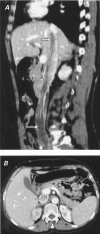

Intravenous leiomyoma with intracaval and intracardiac extension is a rare benign neoplasm affecting women. We report a case in which an intravenous leiomyoma originated from the right iliac vein and extended through the inferior vena cava into the right atrium. The correct diagnosis was made intraoperatively, after resection of the intracardiac extension of the tumor, which was 28 cm in length. At the 2nd stage of the operation, a right common iliac venotomy enabled the removal of all residual tumor from the inferior vena cava.